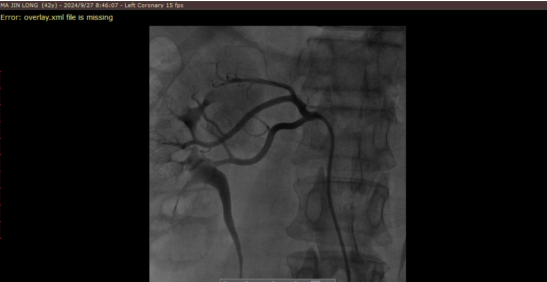

造影图

心脏及泛血管医学诊疗中心团队制定了周密的手术方案,经过充分的术前准备,9月27日7时,患者被推入手术室。在王伟民教授指导下,在先进的医疗设备辅助下,杨毅宁、李国庆、心内四病区副主任余小林、心内四病区副主任郭自同等专家组成的手术团队巧妙地将一根细长的导管精准送入患者肾动脉区域,随后精准操作射频能量,对患者大于等于3mm的肾动脉交感神经进行了细致入微的消融治疗,共有效消融靶点63个。整个手术用时仅一个小时,患者术后血压平稳,安返病房。